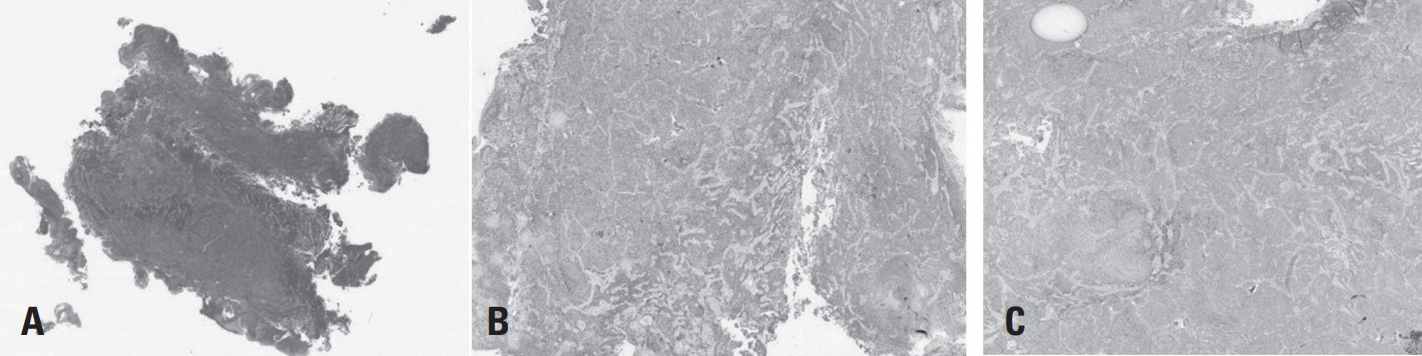

Initial thoracic spine X-ray and CT scans did not show any suspicious findings indicative of a tumor. However, thoracic spine MRI revealed an intradural extramedullary tumor measuring approximately 0.9×1.4×2.5 cm at the T6–7 level. The lesion appeared iso- to hypointense on T2-weighted images, isointense on T1-weighted images, and showed homogeneous enhancement on contrast-enhanced T1-weighted images. It was located at the posterolateral aspect of the spinal cord (Fig. 1. A-D).

In our case, the patient presented with a 7-month history of progressive motor weakness and radiating pain. Magnetic resonance imaging is considered the gold standard for diagnosis, with typical findings including hyperintensity on T2-weighted images and heterogeneous enhancement on contrast-enhanced T1-weighted images.9) However, in this case, the lesion appeared isointense on both T2- and T1- weighted images and exhibited homogeneous enhancement post-contrast, making preoperative suspicion of glioblastoma difficult. This highlights the necessity of histopathological confirmation for accurate diagnosis.

Fig. 1.

Preopertive MRI showing an intradural extramedullary tumor at the T6-7 level. (A) The lesion appears iso- to hypointense on T2WI (B) Isointense on T1W1 and (C, D) shows homogeneous enhancement on contrast-enhanced T1W1.

Fig. 1. Preopertive MRI showing an intradural extramedullary tumor at the T6-7 level. (A) The lesion appears iso- to hypointense on T2WI (B) Isointense on T1W1 and (C, D) shows homogeneous enhancement on contrast-enhanced T1W1.